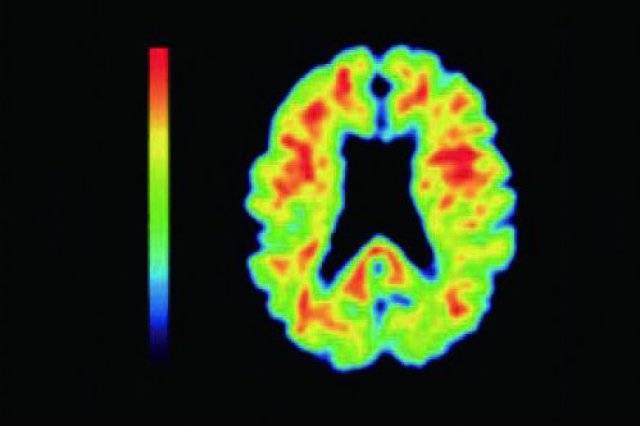

アルツハイマー型認知症に新薬「レカネマブ」が登場